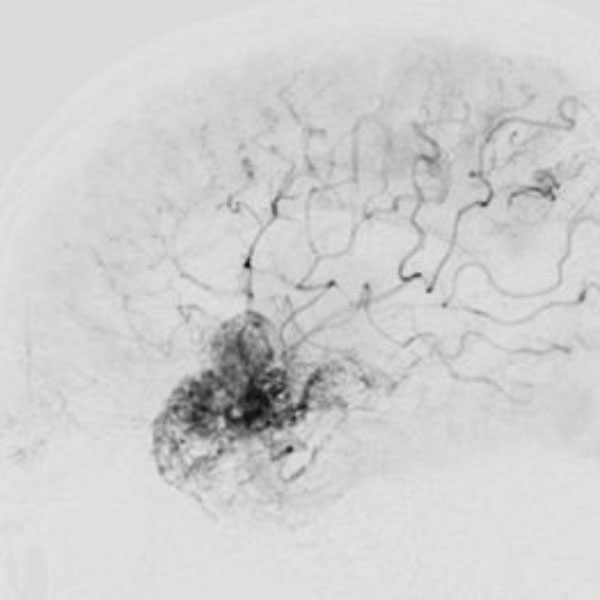

脳血管撮影

手術前

手術後